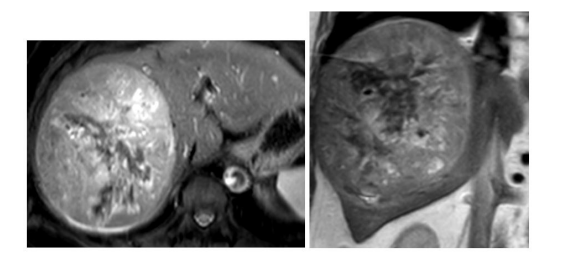

MRI showed significant fatty infiltration of the liver with moderate sized heterogeneous subcapsular lesion in segment VII/VI abutting the right dome of diaphragm. Heterogeneously hyperintense on the T2WI and hypointense on the T1WI. There was associated mild intrahepatic biliary radicle dilatation (Figure 1A, B and C).

| Figure 1: A, B and C: Axial and coronal T2WI show lobulated observation in segment VII and VI with heterogenous appearance |